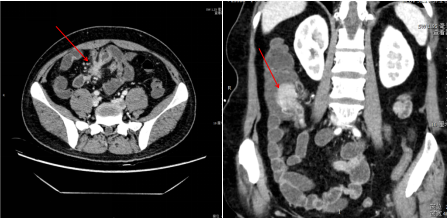

近期我院一例炎症性肠病(考虑克罗恩病)通过增强CT检查及CTE后处理得到明确诊断。

克罗恩病伴内瘘形成 淋巴瘤